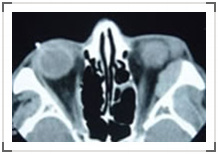

视神经脑膜瘤是起源于视神经脑膜细胞的良性肿瘤,好发于中年女性。典型的脑膜瘤四联征为:视力丧失、眼球突出、继发性视神经萎缩和视神经睫状静脉。另外,眶内脑膜瘤还可来源于蝶骨嵴脑膜细胞或由颅内肿瘤蔓延所致。B超显示视神经增粗,CT可见视神经管状增粗,内部可见视神经低密度影,呈现特征性的“车轨状”或“套袖状”改变,肿瘤邻近视神经管处受阻膨大。MRI显示眶内肿瘤形态同CT,但对视神经管内、颅内蔓延的观察优于CT。治疗方式选择同视神经胶质瘤,但脑膜瘤切除很难完全,术后易复发。